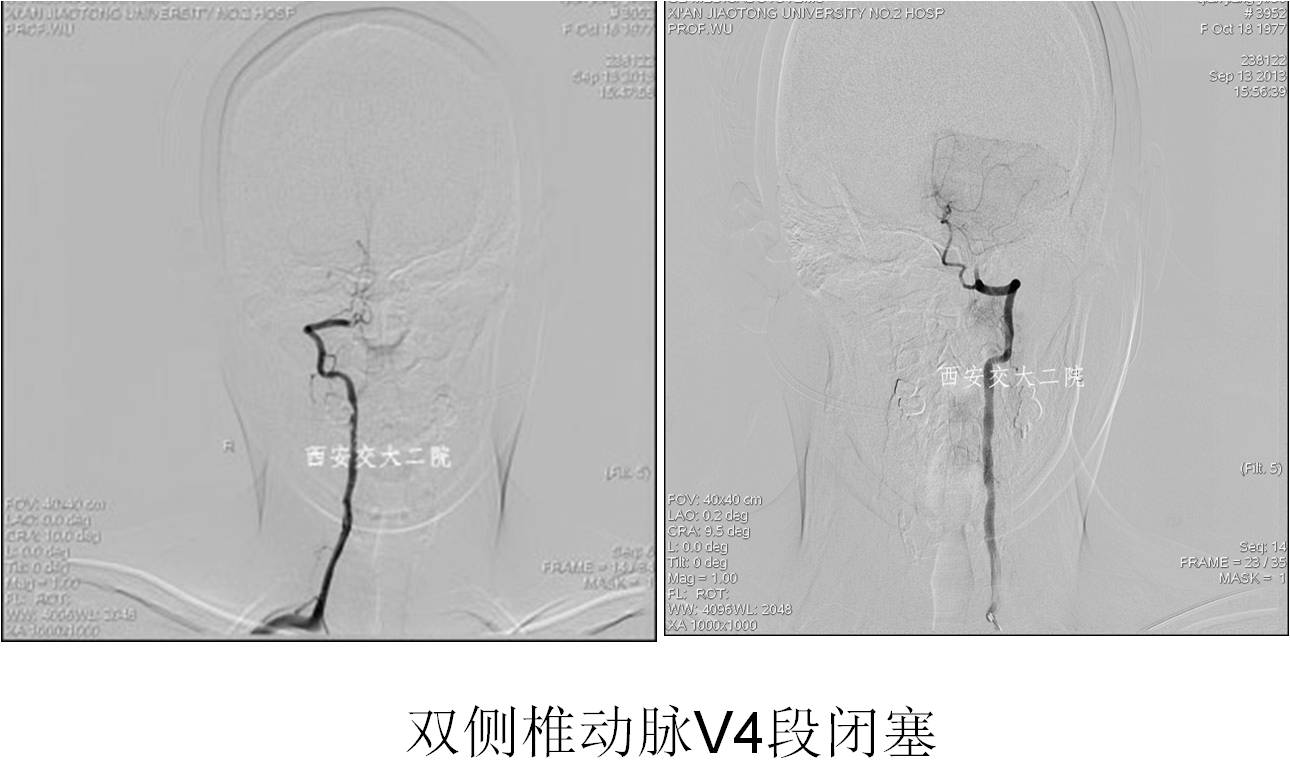

术前DSA

术后DSA